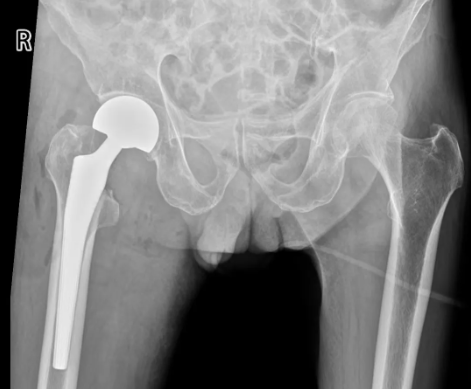

以最短时间完成各项检查,CT等检查显示右股骨颈骨折,收入老年髋部骨折一体化治疗病房。迅速完善心脏彩超、肺部CT、双下肢动静脉彩超及血象等常规检查。创伤骨科主任、副主任医师周占锋带领创伤救治团队立即对杨爷爷进行查体及病情评估。

在稳定原有疾病的基础上,黄金时间内完成手术治疗。考虑杨爷爷年龄较大,基础疾病较多,立即联系呼吸与危重症医学科、心血管内科、麻醉与围术期医学科、神经内科等,启动多学科会诊小组对患者进行评估及术前干预。杨爷爷入院不到24小时就完成了右侧人工股骨头置换术,手术时间约1小时左右。术后,杨爷爷恢复良好,无明显疼痛感。术后第二天,开始扶助行器下地锻炼。目前杨爷爷已康复出院。“现在的医疗水平真是太先进了,真没想到年纪这么大了,还能做手术,而且一点都不痛,这在以前是想都不敢想的事情。”